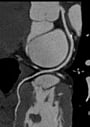

Cardiovascular imaging is one area that has enthusiastically adopted iterative reconstruction because of these benefits. “In the cardiovascular system, filtered back projection causes blooming or beam hardening artifacts of high-density structures such as coronary artery calcifications or coronary artery stents,” said Schoepf, who presented on iterative reconstruction in cardiac imaging at the Society of Cardiovascular Computed Tomography’s (SCCT) 9th annual scientific meeting in July. “It makes it very difficult to gauge the significance of a blockage or narrowing of the heart vessels, and to determine if a stent that was deployed in the heart vessels of the patient is still patent or not.”

Although iterative construction does not completely eliminate the problem, Schoepf said it substantially reduces the artifacts that arise from coronary calcifications and metallic stent struts, so physicians have a better chance of determining which narrowing of the coronary arteries is actually significant and whether stents are still patent.